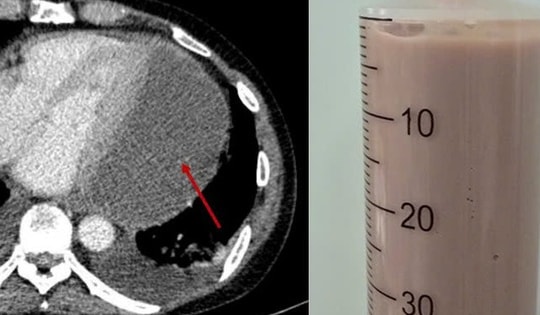

'Mở mắt là uống rượu', người đàn ông nôn ra cả lít máu

Trưa 23/2 (mùng 7 Tết), Khoa Cấp cứu – Bệnh viện Bệnh Nhiệt đới Trung ương tiếp nhận bệnh nhân nam N.C.C. (50 tuổi, ở Hải Phòng) bị xuất huyết tiêu hóa ồ ạt.